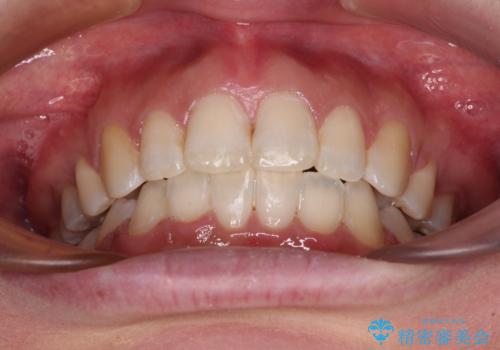

2年ほどインビザラインを使用しましたが、どうしても歯の移動がマウスピースに追随せず、全顎ワイヤー矯正へ切り替えました。

ワイヤー装着後は2年弱で、しっかりと仕上げることができました。